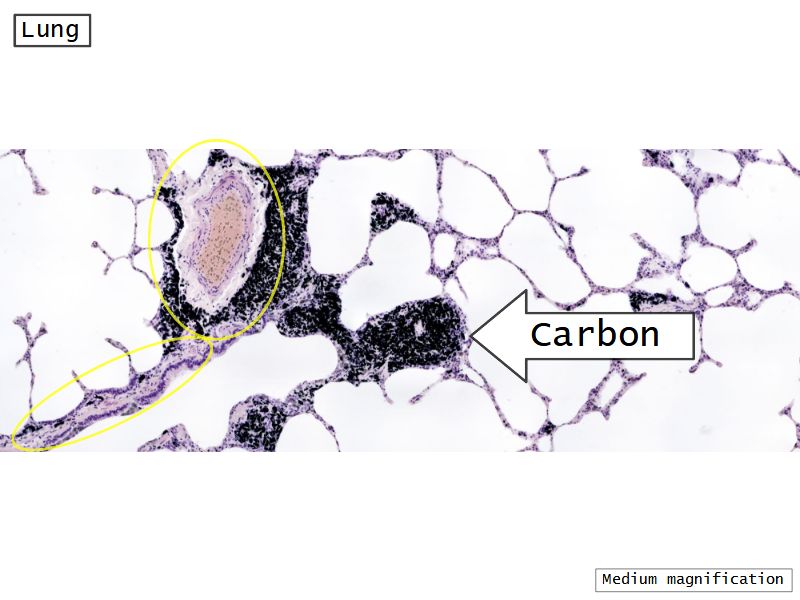

Respiratory epithelium